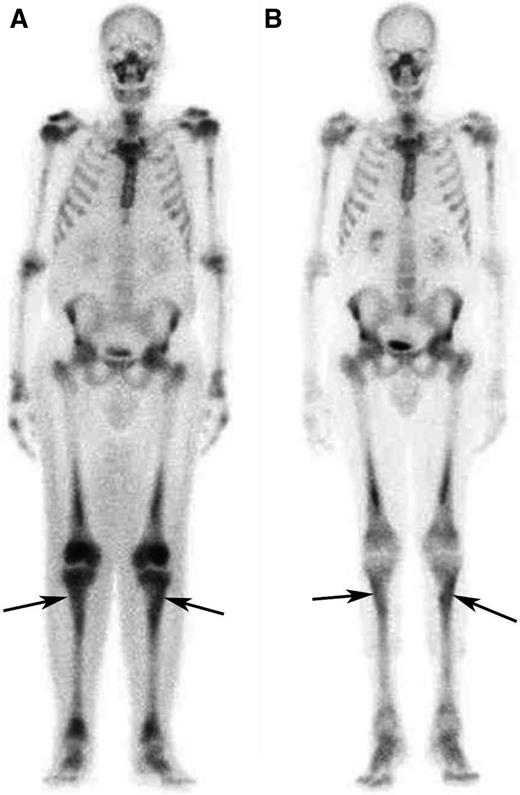

The remaining 8 patients showed PRs of at least one involved site. Retroperitoneal lesions regressed partially in 4/8 cases and completely in 1/8 (Figure 1 and supplemental Figure 2): at last follow-up, only 2 patients had double-J ureteral stents, and the patient with repeat bowel obstructions (patient #1) no longer developed such complications. Cardiovascular lesions improved in 3/4 cases: the 2 patients with severe pericarditis (one of whom was previously described28 ) underwent pericardiocentesis and remained free of pericardial effusion over the entire follow-up (Figure 1). Bone disease usually remained stable, although an improvement at 99Tc-scintigraphy was observed in 3 cases (Figure 2). CNS lesions progressed in patient #6 and stabilized in patient #3, whereas in patient #7 there was no recurrence of the surgically excised brain mass, and the remaining nodules showed partial regression (supplemental Figure 3). Lung involvement stabilized in all cases. The outcome of the remaining disease manifestations is reported in Table 2. Systemic symptoms improved in most patients; the only patient who experienced persistent systemic manifestations was patient #8. C-reactive protein levels also tended to decrease over time (supplemental Figure 4).

Response to treatment in the long bones assessed by bone scintigraphy. (A) Whole-body 99Tc-bone scintigraphy performed before treatment and (B) after 12 months of treatment with SRL and PDN in patient #5. The scans show a significant reduction in tracer uptake especially in long bones such as the tibias (arrows) and the femurs.